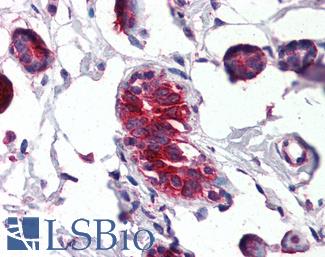

Napsin A

NAPSIN1 Antibody (TMU-Ad02) – IHC of Napsin1 on human lung adenocarcinoma. This image was taken for the unconjugated form of this product. Other forms have not been tested.